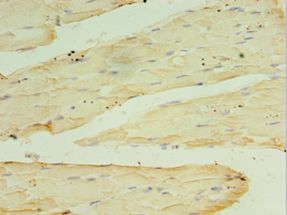

- Experimental details

- Immunohistochemistry of paraffin-embedded human skeletal muscle using antibody at 1:100 dilution.